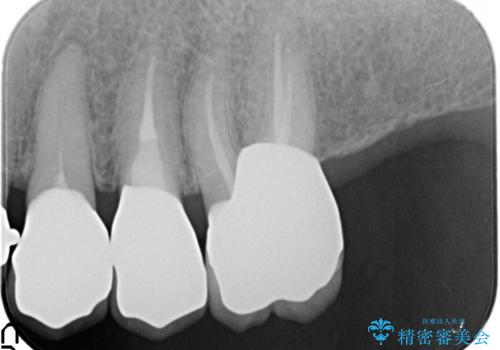

- 奥歯がなくて咬めないのと、全体的に見た目をよくしたいとのことで来院されました。

下顎の両側の奥歯が欠損しており、入れ歯をお持ちでしたが、うまく咬めずにほとんど使用していない状態でした。

上顎は全体的にクラウンの入れ替えと、下顎はインプラントの提案もしましたが、希望されなかったのでノンクラスプデンチャーの製作をする治療計画としました。

奥歯が欠損しており、上下の前歯が強く咬合する可能性があったので、上顎前歯の裏側は金属のものにしました。

お忙しい方でしたので、治療が終了するまでにじかんがかかってしまいましたが、奥歯でもしっかり咬めるようになったと喜んでいただけました。